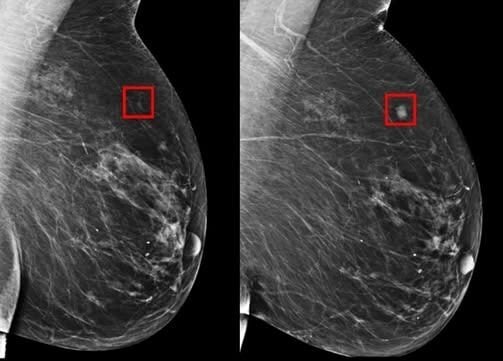

A inteligência artificial que pode salvar milhões de vidas: ela detecta o câncer de mama até cinco anos antes

O diagnóstico precoce é o pilar mais importante no combate a condições graves da mama, elevando significativamente as chances de tratamento bem-sucedido e cura. Tradicionalmente, a mamografia é a principal ferramenta de rastreamento, mas sua eficácia é limitada pela capacidade humana de identificar padrões sutis e pelo fato de detectar a condição apenas quando ela já está presente.

Recentemente, a Inteligência Artificial (IA) emergiu como um divisor de águas na área de saúde feminina. Softwares avançados, treinados com milhões de imagens, estão desenvolvendo a capacidade de analisar exames e identificar marcadores de risco anos antes que a lesão se manifeste de forma visível em exames clínicos ou radiológicos. Esta tecnologia não apenas auxilia o trabalho dos médicos, mas promete inaugurar uma era de previsibilidade e intervenção preventiva que pode, literalmente, salvar milhões de vidas.

A IA aplicada ao rastreamento mamário utiliza algoritmos de Aprendizado Profundo ( Deep Learning ), uma subcategoria do Machine Learning, para executar tarefas que imitam a inteligência humana em reconhecimento de padrões, mas em uma escala e velocidade incomparáveis.

1. Treinamento com Big Data: O sistema é alimentado com vastos conjuntos de dados (milhões de mamografias, ressonâncias magnéticas e dados clínicos). Durante o treinamento, ele aprende a associar padrões radiológicos sutis — como microcalcificações de difícil percepção, mudanças na densidade do tecido ou texturas específicas — a resultados futuros, ou seja, se a paciente desenvolveu ou não a condição anos depois.

2. Identificação de Biomarcadores de Risco: Enquanto um radiologista humano busca a lesão visível (lesão estabelecida), a IA busca biomarcadores radiômicos e padrões de risco que indicam a probabilidade de desenvolvimento futuro. Ela consegue detectar alterações mínimas na arquitetura do tecido que precedem a formação de um tumor detectável.

3. Apoio à Decisão Clínica: O resultado da IA não é um diagnóstico final, mas sim um mapa de risco. A IA marca as áreas de preocupação e atribui uma pontuação de risco. Isso permite que o médico priorize exames de pacientes com risco elevado, solicite monitoramento mais frequente ou utilize outras modalidades de imagem. O sistema atua como um “segundo par de olhos” ultra-sensível.